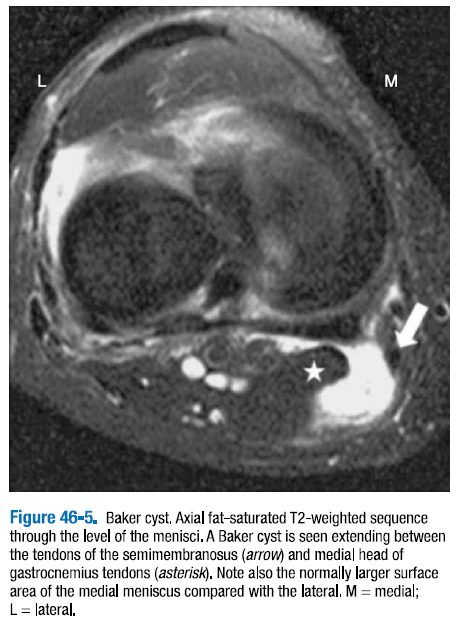

베이커 낭종 또는 슬와 낭종은 반막근(semimembranosus)과 비복근(gastrocnemius)의 내측두의 힘줄 사이의 슬관절 후방으로 이어져 있는 점액낭이다. (그림 46-5) 베이커 낭종의 존재는 만성적이거나 재발하는 슬관절 삼출액을 암시하고 특히 반월판 파열과 연골 결손과 같은 관절내의 병소를 찾도록 하는 징후이다.

△ 그림 46-5. 베이커 낭종. 반월판의 레벨을 통과하는 축면 지방 포화 T2 강조 시퀀스

베이커 낭종은 반막근건(화살표)과 비복근건의 내측두(별표) 사이에서 확대된 것으로 보인다. 외측과 비교하여 내측 반월판이 정상적으로 더 큰 표면적을 가짐을 또한 주목할 것. M = 내측, L = 외측